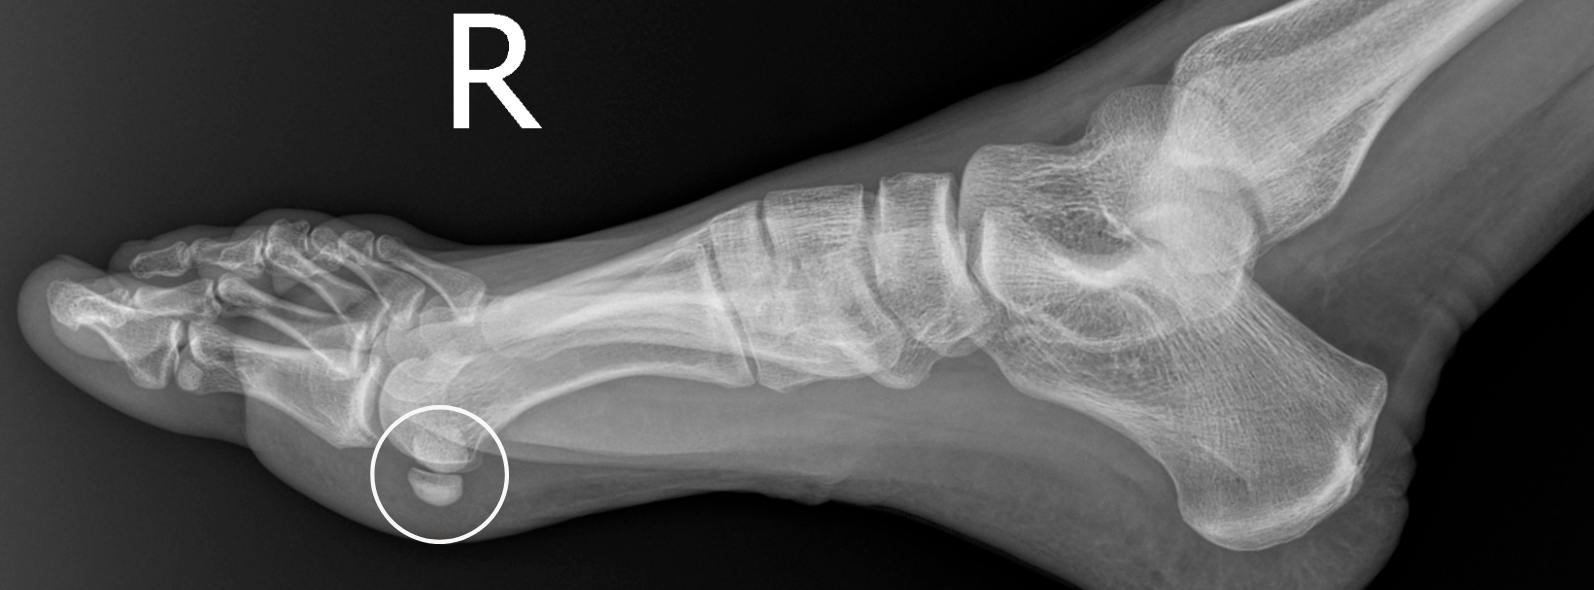

Sesamoiditis Witty, Pask & Buckingham Pain Under Foot Below Big Toe Web the most common and obvious symptom of sesamoiditis is pain in the ball of the foot: Sharp, aching or burning pain in the ball of your foot — the. Web pain in the big toe can have several causes. Some are from injuries, systemic medical conditions, or repeated strain over time. Web what does pain in the big toe. Pain Under Foot Below Big Toe.

Pain under the big toe joint? It might be your Sesamoids. — Foot & Ankle Pain Under Foot Below Big Toe Sharp, aching or burning pain in the ball of your foot — the. Web pain under the foot near the big toe is the most common indicator of sesamoiditis. Pain in the big toe can indicate an injury or an underlying health condition. Web what does pain in the big toe indicate? Web the most common and obvious symptom of. Pain Under Foot Below Big Toe.